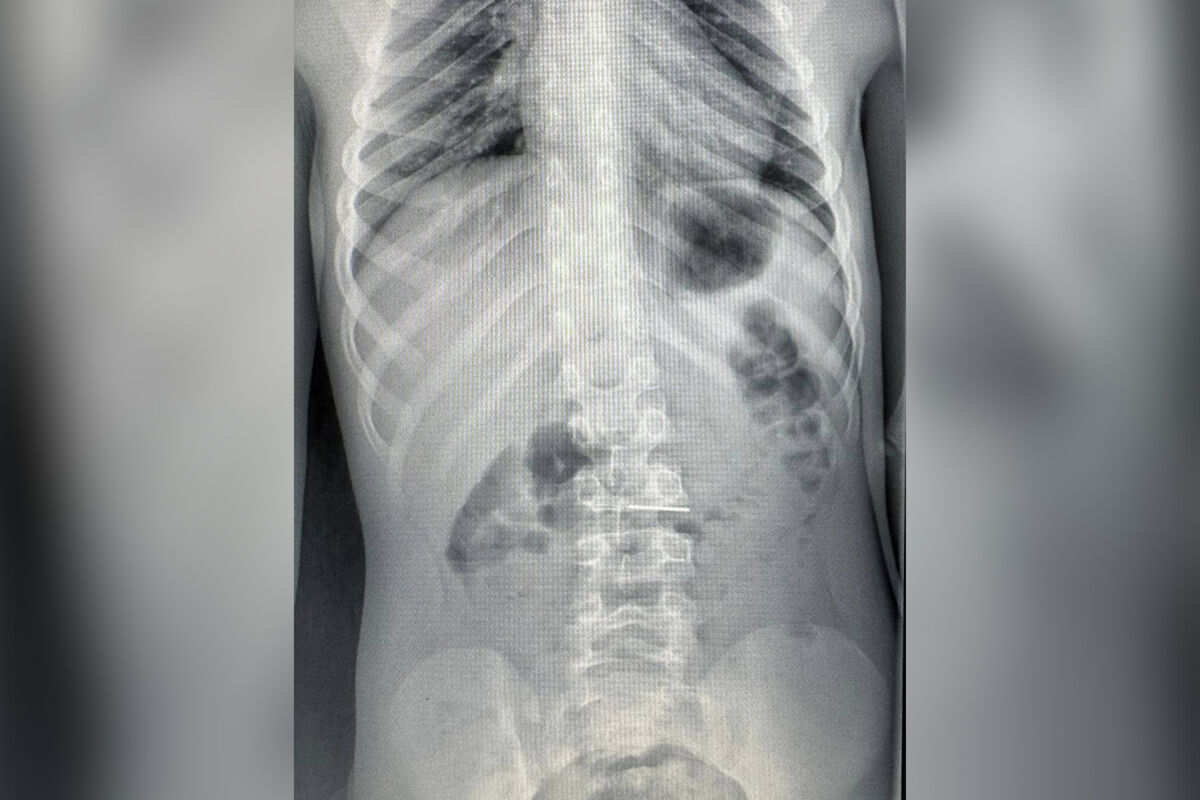

Врачи Детского центра имени Л.М. Рошаля спасли шестилетнего мальчика, который проглотил иголку. Об этом сообщили в пресс-службе минздрава Московской области.

Маленького пациента доставили в больницу на скорой помощи. Обследование показало, что инородный предмет опустился в желудок ребенка.

«С помощью биопсийных щипцов эндоскописты переместили иголку из двенадцатиперстной кишки в желудок, откуда уже безопасно извлекли из тела ребенка», — рассказали в пресс-службе ведомства, добавив, что на манипуляцию врачам потребовалось полчаса.